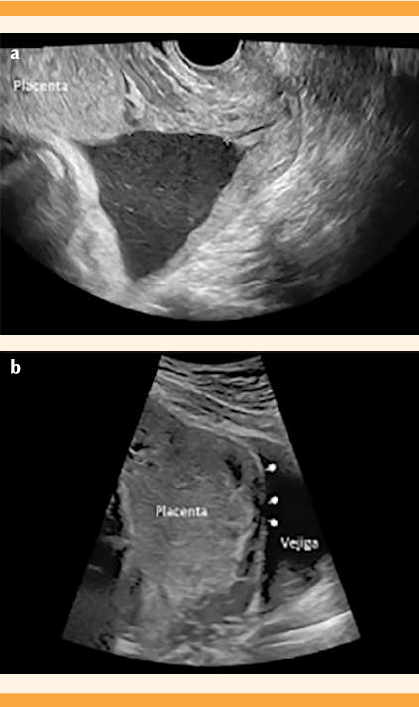

Paciente de 20 años, con antecedente de 3 embarazos y 2 cesáreas; sin procedimientos quirúrgicos y con un embarazo gemelar bicorial biamniótico atendida en el Departamento de Medicina Fetal e Imagenología del Hospital de Ginecoobstetricia del Centro Médico Nacional de Occidente. En la valoración ultrasonográfica (equipo GE Voluson E6 y transductor convexo 3.5 Hz) efectuada a las 36 semanas se detectaron dos fetos vivos y dos placentas, una en el fondo uterino y la otra con inserción en el cuerpo uterino, en su cara anterior e inferior, con sospecha de inserción marginal al orificio cervical interno. Se descartó el diagnóstico de placenta previa por vía vaginal, mediante el transductor endocavitario de 7.5 Hz, con borde inferior placentario a más de 30 mm del orificio cervical interno (Figura 1a). Se detectaron signos ecográficos de acretismo placentario. En la revisión trans-abdominal se advirtieron: pérdida de la línea hipoecoica, adelgazamiento del miometrio, abombamiento hacia la vejiga, interrupción de la pared vesical (Figura 1b) e hipervascularidad útero-vesical (Figura 2a). Por vía transvaginal: hipervascularidad subplacentaria e hipervascularidad útero-vesical con Doppler 3D (Figura 2b). No se observaron lagunas placentarias, vasos alimentadores de lagunas ni hipervascularidad intraplacentaria.

Figura 1 (a) Ultrasonido transvaginal bidimensional, que muestra el borde placentario inferior (caliper verde) a 3.57 cm del orificio cervical interno (caliper amarillo). (b) Ultrasonido transabdominal, que identifica los signos ecográficos de acretismo placentario: pérdida de la línea hipoecoica, adelgazamiento del miometrio, abombamiento hacia la vejiga, interrupción de la pared útero-vesical (apuntadores).